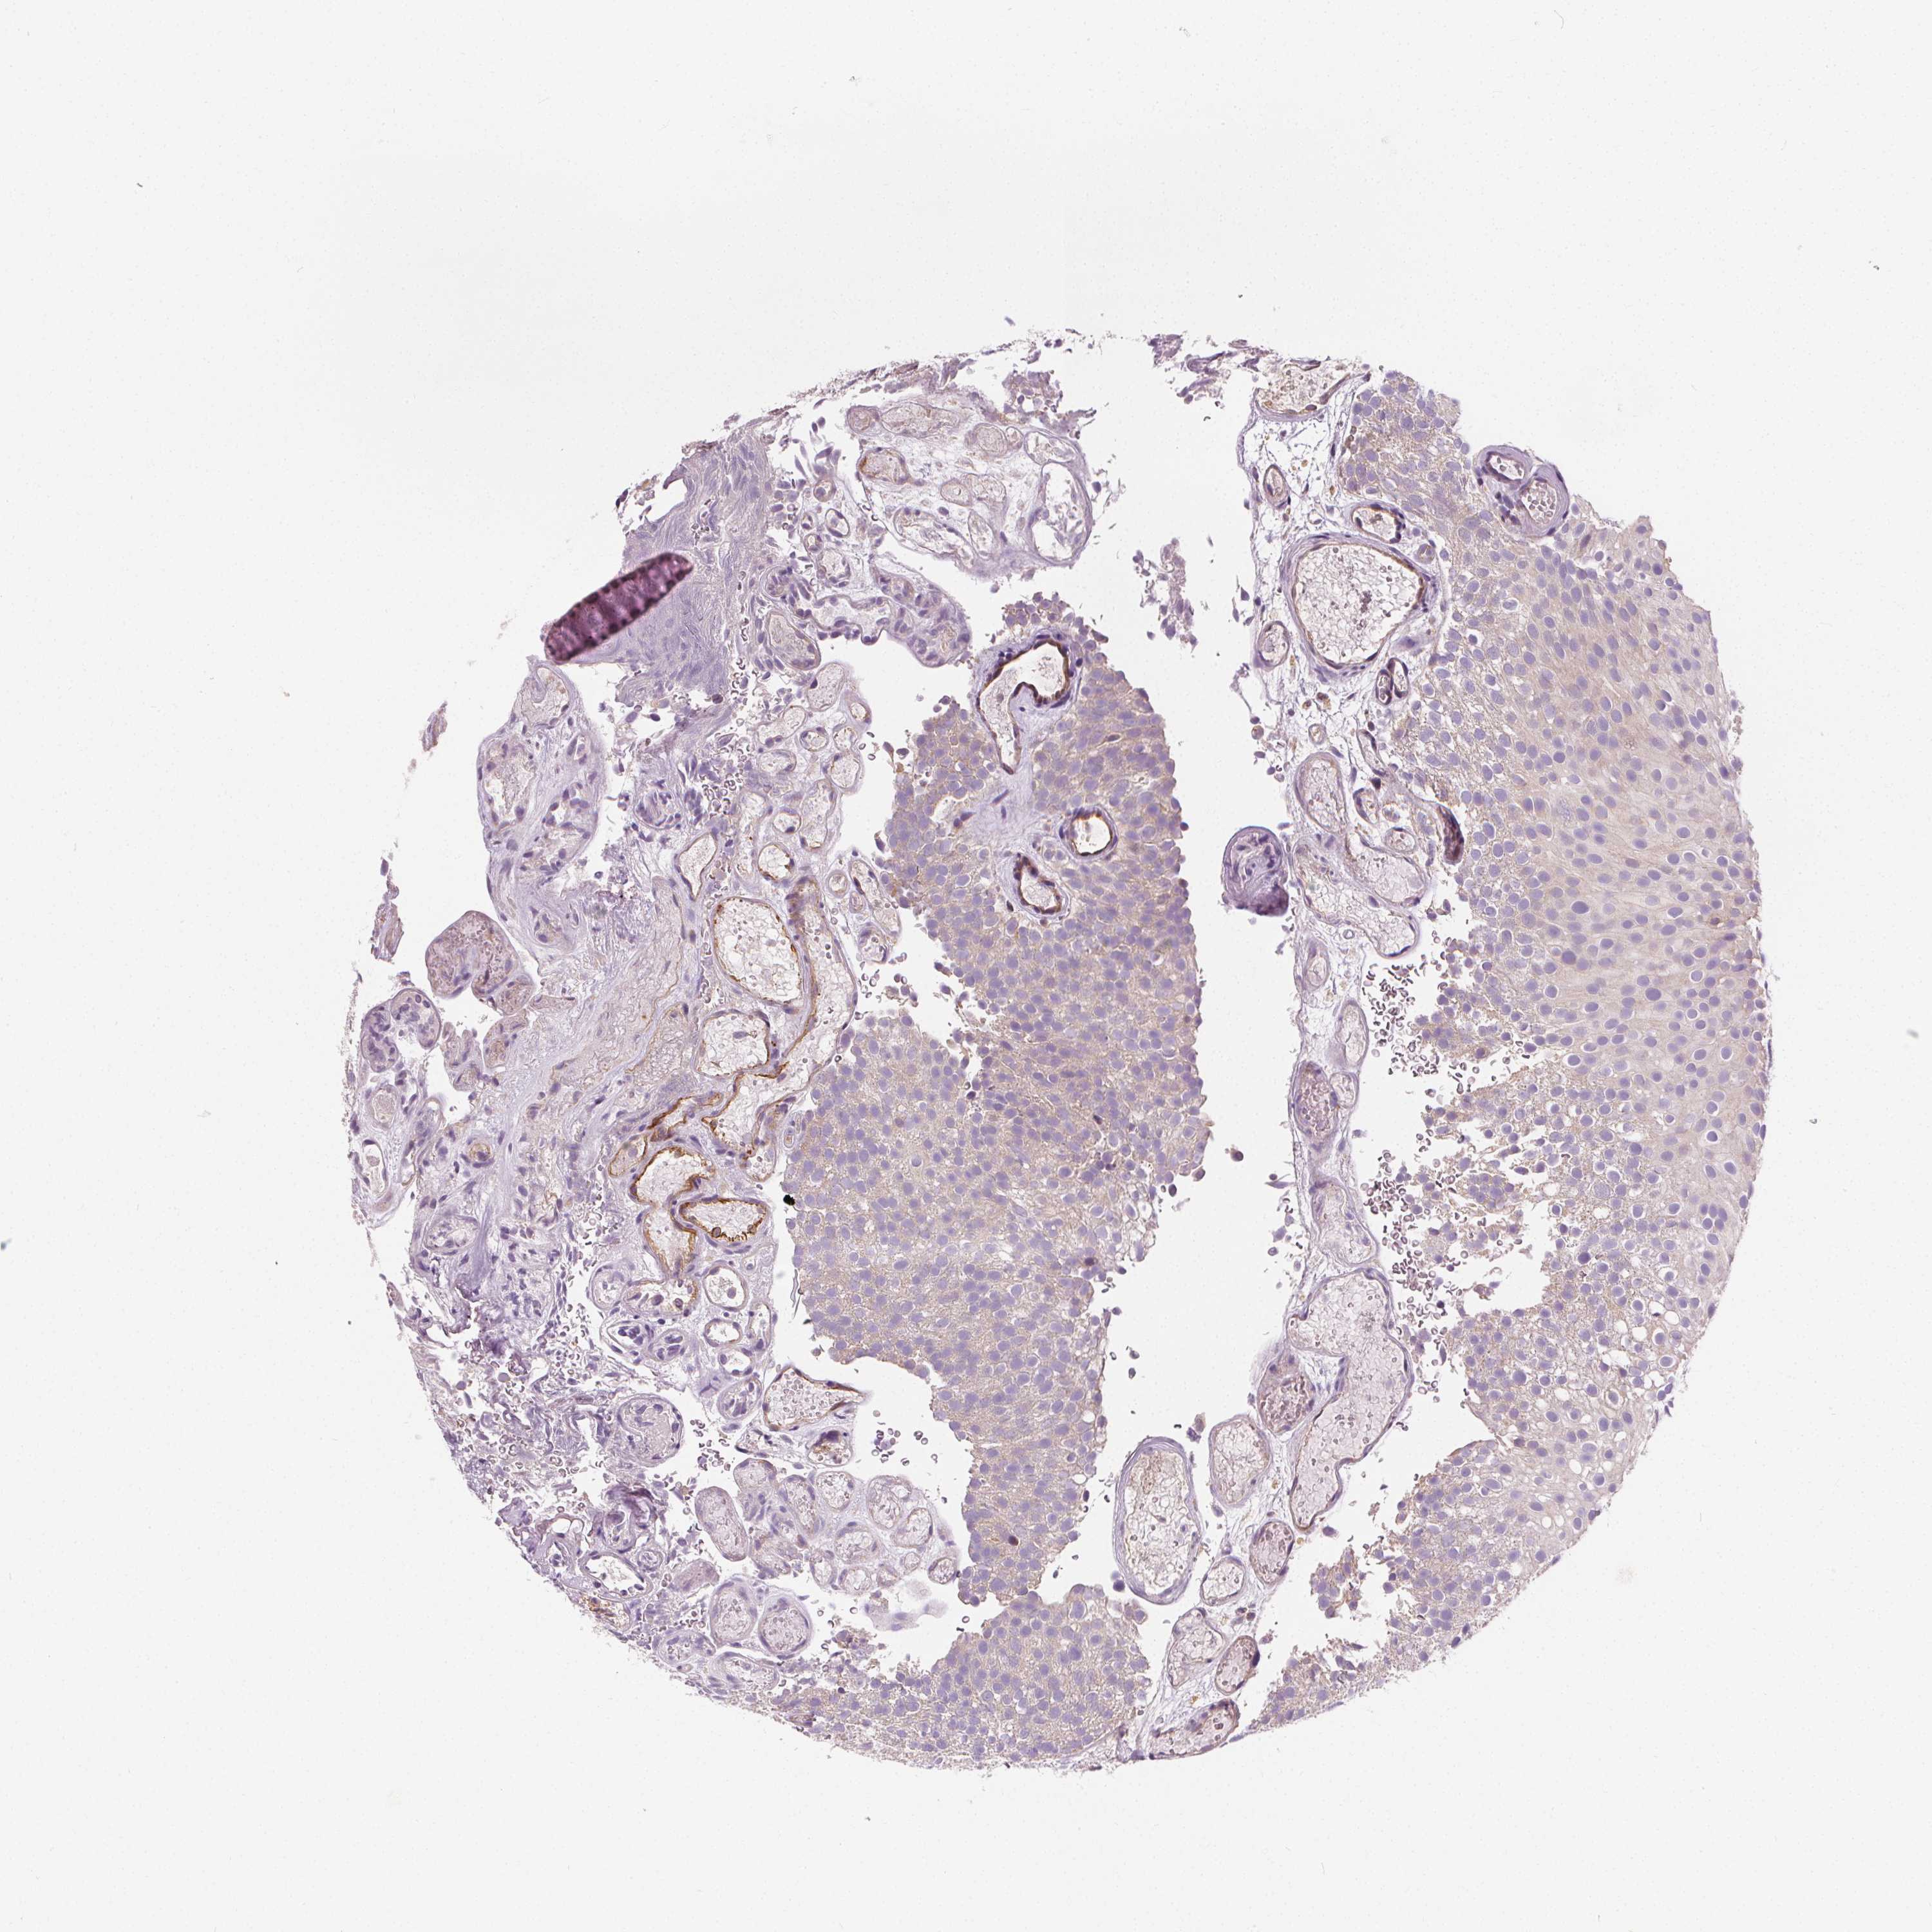

UROTHELIAL CANCER - Protein expressioni

A mouse-over function shows sample information and annotation data. Click on an image to view it in a full screen mode. Samples can be filtered based on level of antibody staining by selecting one or several of the following categories: high, medium, low and not detected. The assay and annotation is described here.

Note that samples used for immunohistochemistry by the Human Protein Atlas do not correspond to samples in the TCGA dataset.

Antibody stainingi

Antibody staining in the annotated cell types in the current human tissue is reported as not detected, low, medium, or high, based on conventional immunohistochemistry profiling in selected tissues. This score is based on the combination of the staining intensity and fraction of stained cells.

Each image is clickable and will lead to virtual microscopy that enables deeper exploration of all samples and also displays staining intensity scores, fraction scores and subcellular localization as well as patient and tissue information for each sample.

Antibody HPA068647

Staining

High

Medium

Low

Not detected

Intensity

Strong

Moderate

Weak

Negative

Quantity

>75%

75%-25%

<25%

None

Location

Urothelial carcinoma, High grade

Urothelial carcinoma, Low grade

Urothelial carcinoma, NOS